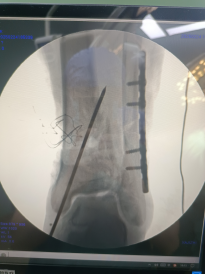

腓骨予以重建內(nèi)固定板固定。

三臂十一軸機器人輔助器牽引,安裝外固定架,透視檢查骨折端對位對線良好。